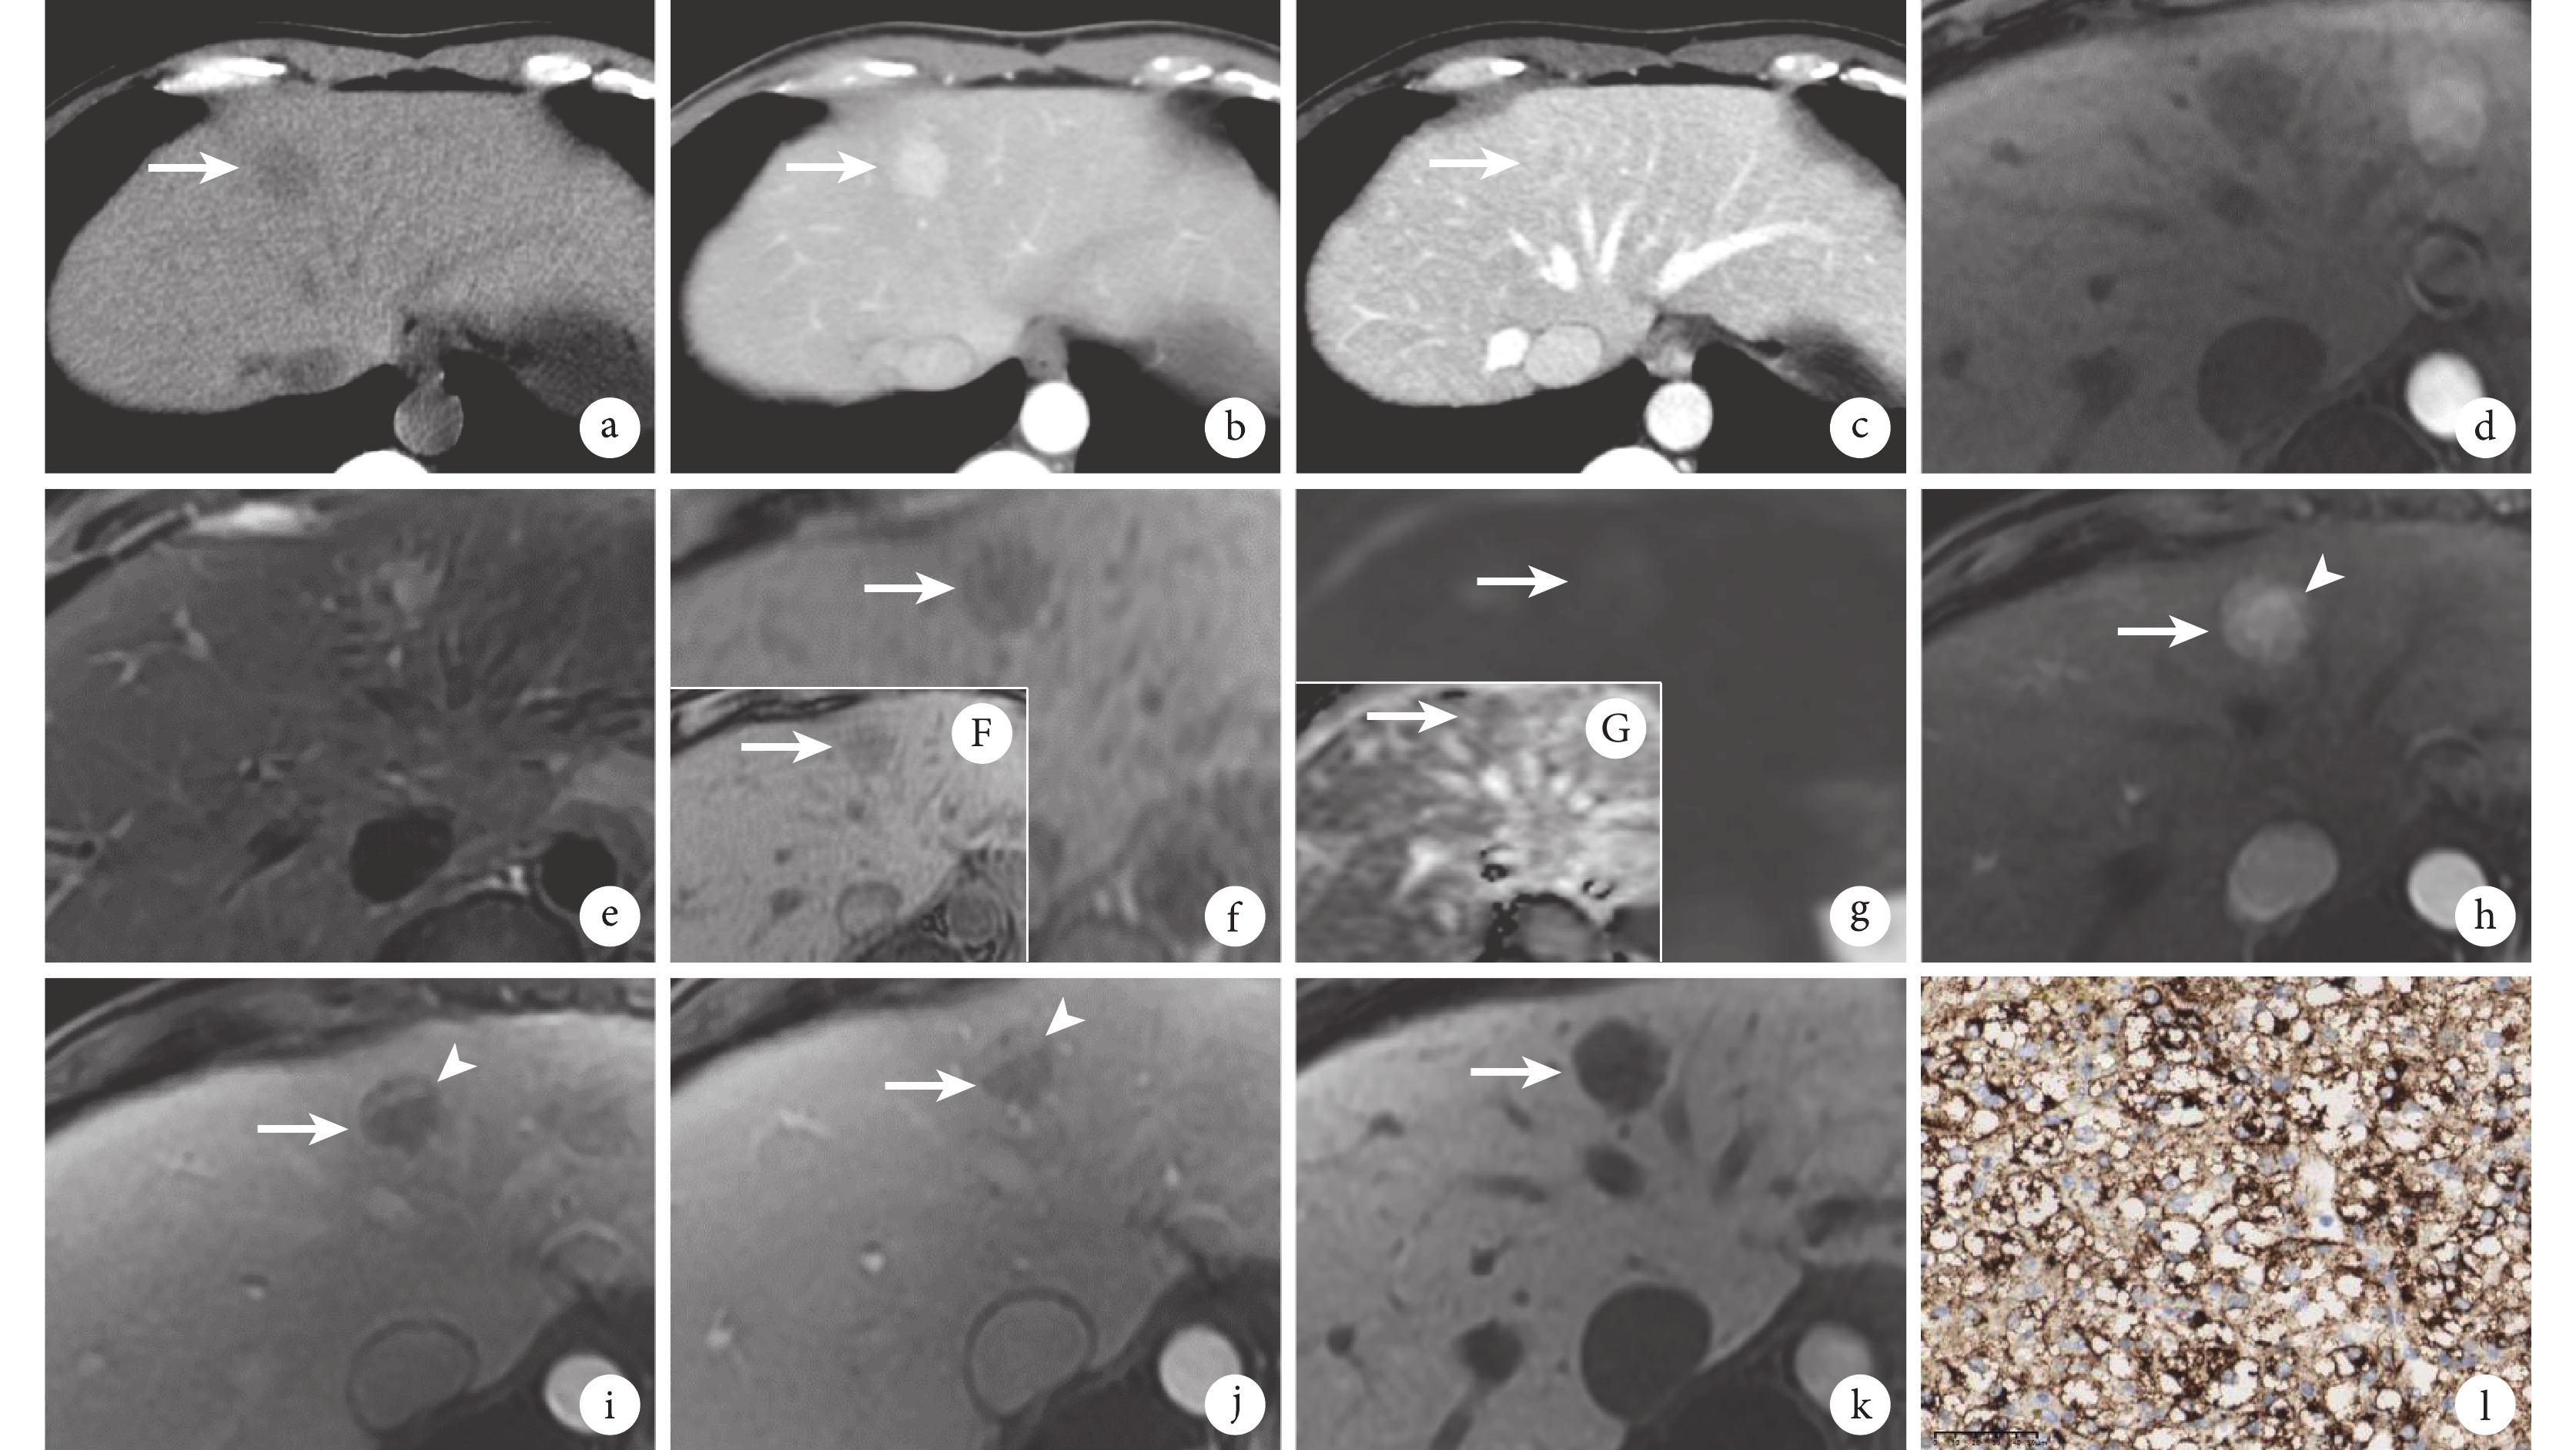

a~c:肝臟CT掃描軸位圖像,平掃見肝S4孤立性稍低密度結節、邊界欠清(a),增強掃描見動脈晚期明顯強化(b)、門靜脈期部分廓清(c);d~k:MRI肝臟軸位圖像,平掃見T1WI低信號(d)、T2WI稍高信號結節影(e),T1WI同相位(f)和反相位(F)圖像未見明顯變化,b=1 000 s/mm2時DWI呈稍高信號(g)、ADC呈不均勻稍低信號(G),增強掃描動脈晚期較均勻明顯強化(h)、門靜脈期(i)和延遲期(j)病灶廓清,可見持續強化小血管影及邊緣環形強化影,病灶肝膽期呈低信號(k);l:腫瘤人黑色素瘤單克隆抗體 45(human melanoma black 45,HMB45)陽性(免疫組織化學染色 ×40)。圖中白箭示病灶、白箭頭示病灶內持續強化血管影,圖g~i中見腹主動脈搏動偽影

該患者腹部CT平掃見肝S4孤立性稍低密度結節,邊界欠清(圖1a);CT增強掃描見動脈晚期明顯強化(圖1b)、門靜脈期部分廓清(圖1c),呈“快進快出”強化方式。MRI肝膽特異性對比劑增強檢查見肝S4 T1加權成像(weighted imaging,WI)低信號(圖1d)、T2WI稍高信號結節影(圖1e);T1WI同相位(圖1f)和反相位(圖1F)信號未見明顯變化,提示無明顯胞內脂質成分;高b值(b=1 000 s/mm2)時擴散加權成像(diffusion-weighted imaging,DWI)呈稍高信號(圖1g),表觀擴散系數(apparent diffusion coefficient,ADC)呈不均勻稍低信號(圖1G),即“輕度水分子擴散受限” ;增強掃描呈“快進快出”強化方式,動脈晚期較均勻明顯強化(圖1h),門靜脈期(圖1i)和延遲期(圖1j)病灶廓清,可見持續強化小血管影(圖1h、1i、1j中白箭頭所示),同時可見門靜脈期和延遲期邊緣環形強化影(圖1i、1j),即“假包膜”征;病灶肝膽期呈低信號(圖1k)。綜合患者年齡、病史及陰性腫瘤標志物,考慮HAML可能性大。

病變部位:肝S4結節。樣本類型:手術切除。病理診斷:HAML。免疫組織化學染色:人黑色素瘤單克隆抗體45(human melanoma black 45,HMB45,圖1l)、T細胞1識別的黑色素瘤抗原(melanoma antigen recognized by T cells 1,MART-1)、平滑肌肌動蛋白(smooth muscle actin,SMA)及CD34均為陽性,Desmin個別陽性,S100、廣譜細胞角蛋白、轉錄因子增強子3(transcription factor enhancer 3,TFE-3)、Hepa、磷脂酰肌醇蛋白聚糖3(glypican-3,GPC-3)及配對盒基因8均為陰性,Ki-67陽性率約10%。